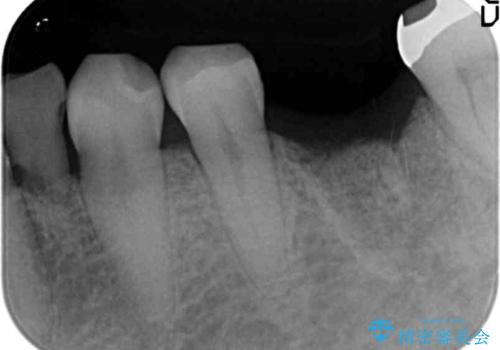

- 強く噛みしめる癖や歯ぎしりにより歯が割れてしまい、抜歯後のインプラント治療を求めて来院されました。

歯に大きな力がかかると、特に大きな銀歯の入った歯や神経治療をしたことのある歯は割れてしまい抜歯を余儀なくされる可能性が高まります。